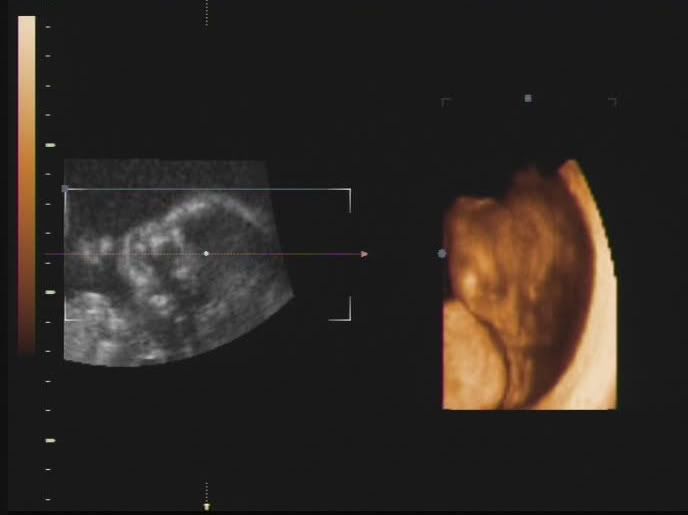

Hola a todos!, me presentaría, pero todavia no he nacido y no tengo nombre, se supone que lo haré aproximadamente el 26 de Marzo, mis papis (Dinís y Bárbara) acaban de enterarse de que voy a ser una niñita y están pensando en que nombre ponerme, a ellos les gustaría un nombre compuesto ya que es tradición en sus dos familias, pero como tienen un lio del carajo he decidido abrir este blog primero para que les ayudeis con mi nombre, y después para que sigais mi evolución como bebecita.